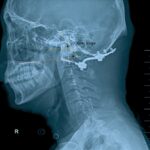

Dear Editor in Chief, We read with great interest the article of Ma et al [1], in which they conducted a retrospective case-control study that enrolled 112 patients who were diagnosed as basilar invagination (BI), to illuminate the diagnostic value of a new angle:...